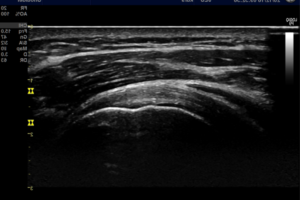

Ultraljud ger både en överlägsen upplösning/detaljrikedom samt möjliggör dynamiska undersökningar i realtid.

Ultraljudsdiagnostik av rörelseapparaten är idag en mycket användbar och tillförlitlig undersökningsmetod som används till akuta skador såväl som långsamt tilltagande överbelastningsskador.

Vid användning av en modern version av ultraljudsutrustning, lik den vi har på MPFysio, fungerar metoden i vissa fall lika bra som magnetröntgen vid undersökning av exempelvis skador i axelns senor, senor i underben och händer m.m.

Ultraljud medför ingen skadlig joniserande strålning och påverkas inte negativt av metalliska föremål såsom proteser, skruvar, plattor etc. För personer med klaustrofobi samt barn som har svårt att ligga still är ultraljud ett bra alternativ till magnetröntgen.